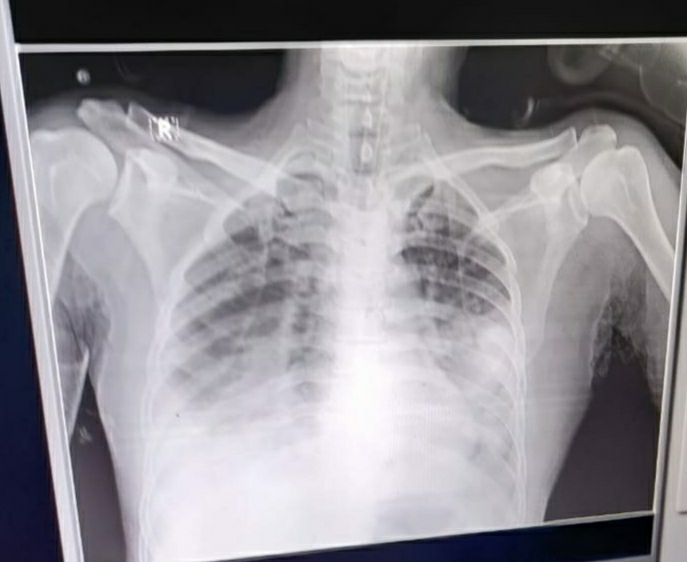

A 42yr old Male with Bilateral Lower lobe consolidation , Necrotising Pneumonia with Pneumothorax, DM- since 4 yrs , Severe Hypovolemia? ACUTE Anterior wall MI? Myocardial depression 2° to Lactic Acidosis? Septic shock / ? Cardiogenic Shock

Radiological investigations:

X ray before thoracocentesis:

X ray after Thoracocentesis:

X ray after shifting him to ICU:

X ray on 25/11/21:

X ray on 26/11/21 5pm:

Bilateral Lower lobe consolidation , Necrotising Pneumonia with Pneumothorax

S/P Needle thoracocentesis (24/12/21)

DM- 4 yrs , Severe Hypovolemia

? ACUTE Anterior wall MI

? Myocardial depression 2° to Lactic Acidosis

? Septic shock / ? Cardiogenic Shock